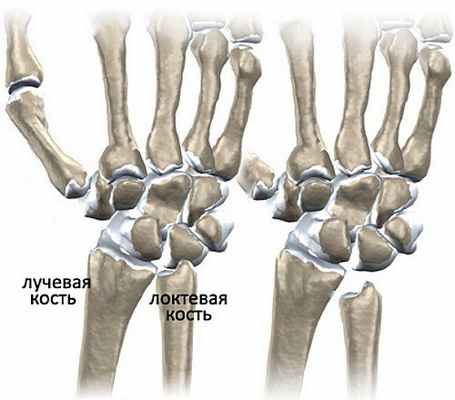

Болезнь Кинбека (Kienböck disease) — это проблема в запястье, связанная с нарушением кровоснабжения полулунной кости. Полулунная — это одна из тех восьми маленьких косточек, которые составляют запястье. В запястье выделяют два ряда: тот, что ближе к предплечью называют проксимальным, другой, который ближе к пальцам — дистальным. Полулунная кость находится в самом центре проксимального ряда, она неразрывно связана с ладьевидной костью, которая соединяет оба ряда запястья. Согласно биомеханическим исследованиям порядка 70% нагрузки на лучезапястный сустав ложатся именно на полулунную кость.

Полулунная кость - одна из восьми костей запястья.

Кости запястья.

Поэтому болезнь Кинбека чаще встречается у людей, чья физическая активность связана с высокой нагрузкой на область лучезапястного сустава. Полулунная кость занимает центральное место в запястье, располагаясь между головчатой костью запястья и лучевой костью, и поэтому больше других костей травмируется при физической нагрузке. Заболевание развивается постепенно, и встречается чаще всего у мужчин рабочих профессий: рубщиков, столяров, слесарей, крановщиков, лиц, работающих с вибрирующими устройствами (отбойные молотки, перфораторы, и т.п.). НО, может возникать и у женщин других специальностей: парикмахер, повар, пекарь, кондитер, косметолог, визажист, массажист и т.п. Чаще всего поражается ведущая рука (у правшей - правая, у левшей - левая) при болезни Кинбека. Еще одна из причин развития болезни Кинбека - врожденная короткая локтевая кость. При таком случае давление на полулунную кость возрастает и может развиться остеонекроз полулунной кости (болезнь Кинбека).

Слева - нормальная длина лучевой и локтевой костей, справа - врожденная короткая локтевая кость.